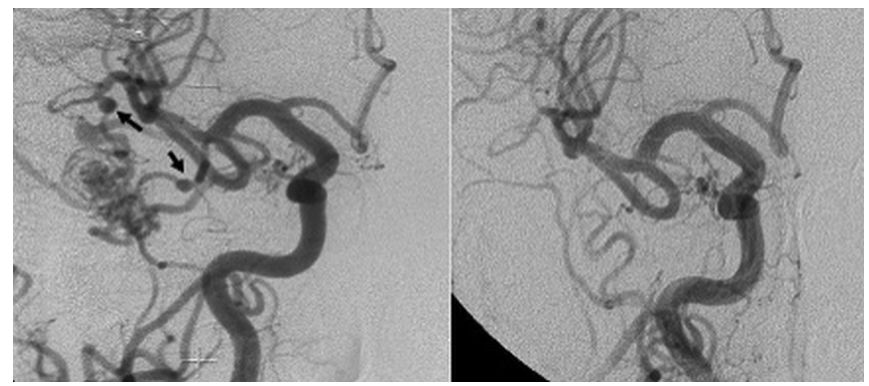

病例二:左图提示该患者为右侧额颞AVM,右侧大脑中动脉 M1 段近端 FAs 较小(箭头)。右图显示GKS 术后 38 个月的常规血管造影显示近端 FAs 几乎完全闭塞。